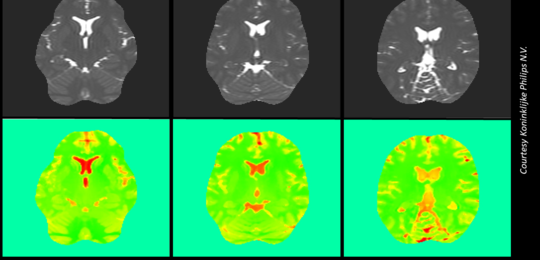

Six pictures showing a human brain scan. Three images in upper row showing black and white pictures of the brain and below these the corresponding EPT images in green with orange indicating tissue sub-types

Quantifying the uncertainty of Electric Properties Tomography in medical imaging

Magnetic Resonance Imaging (MRI) is a diagnostic, mainly qualitative, technique used to visualise the soft tissues of a patient. The application of a strong magnetic field causes the protons in a patient’s hydrogen atoms to align with it. Radiofrequency pulses are then used to force the protons to move out of and back into alig...